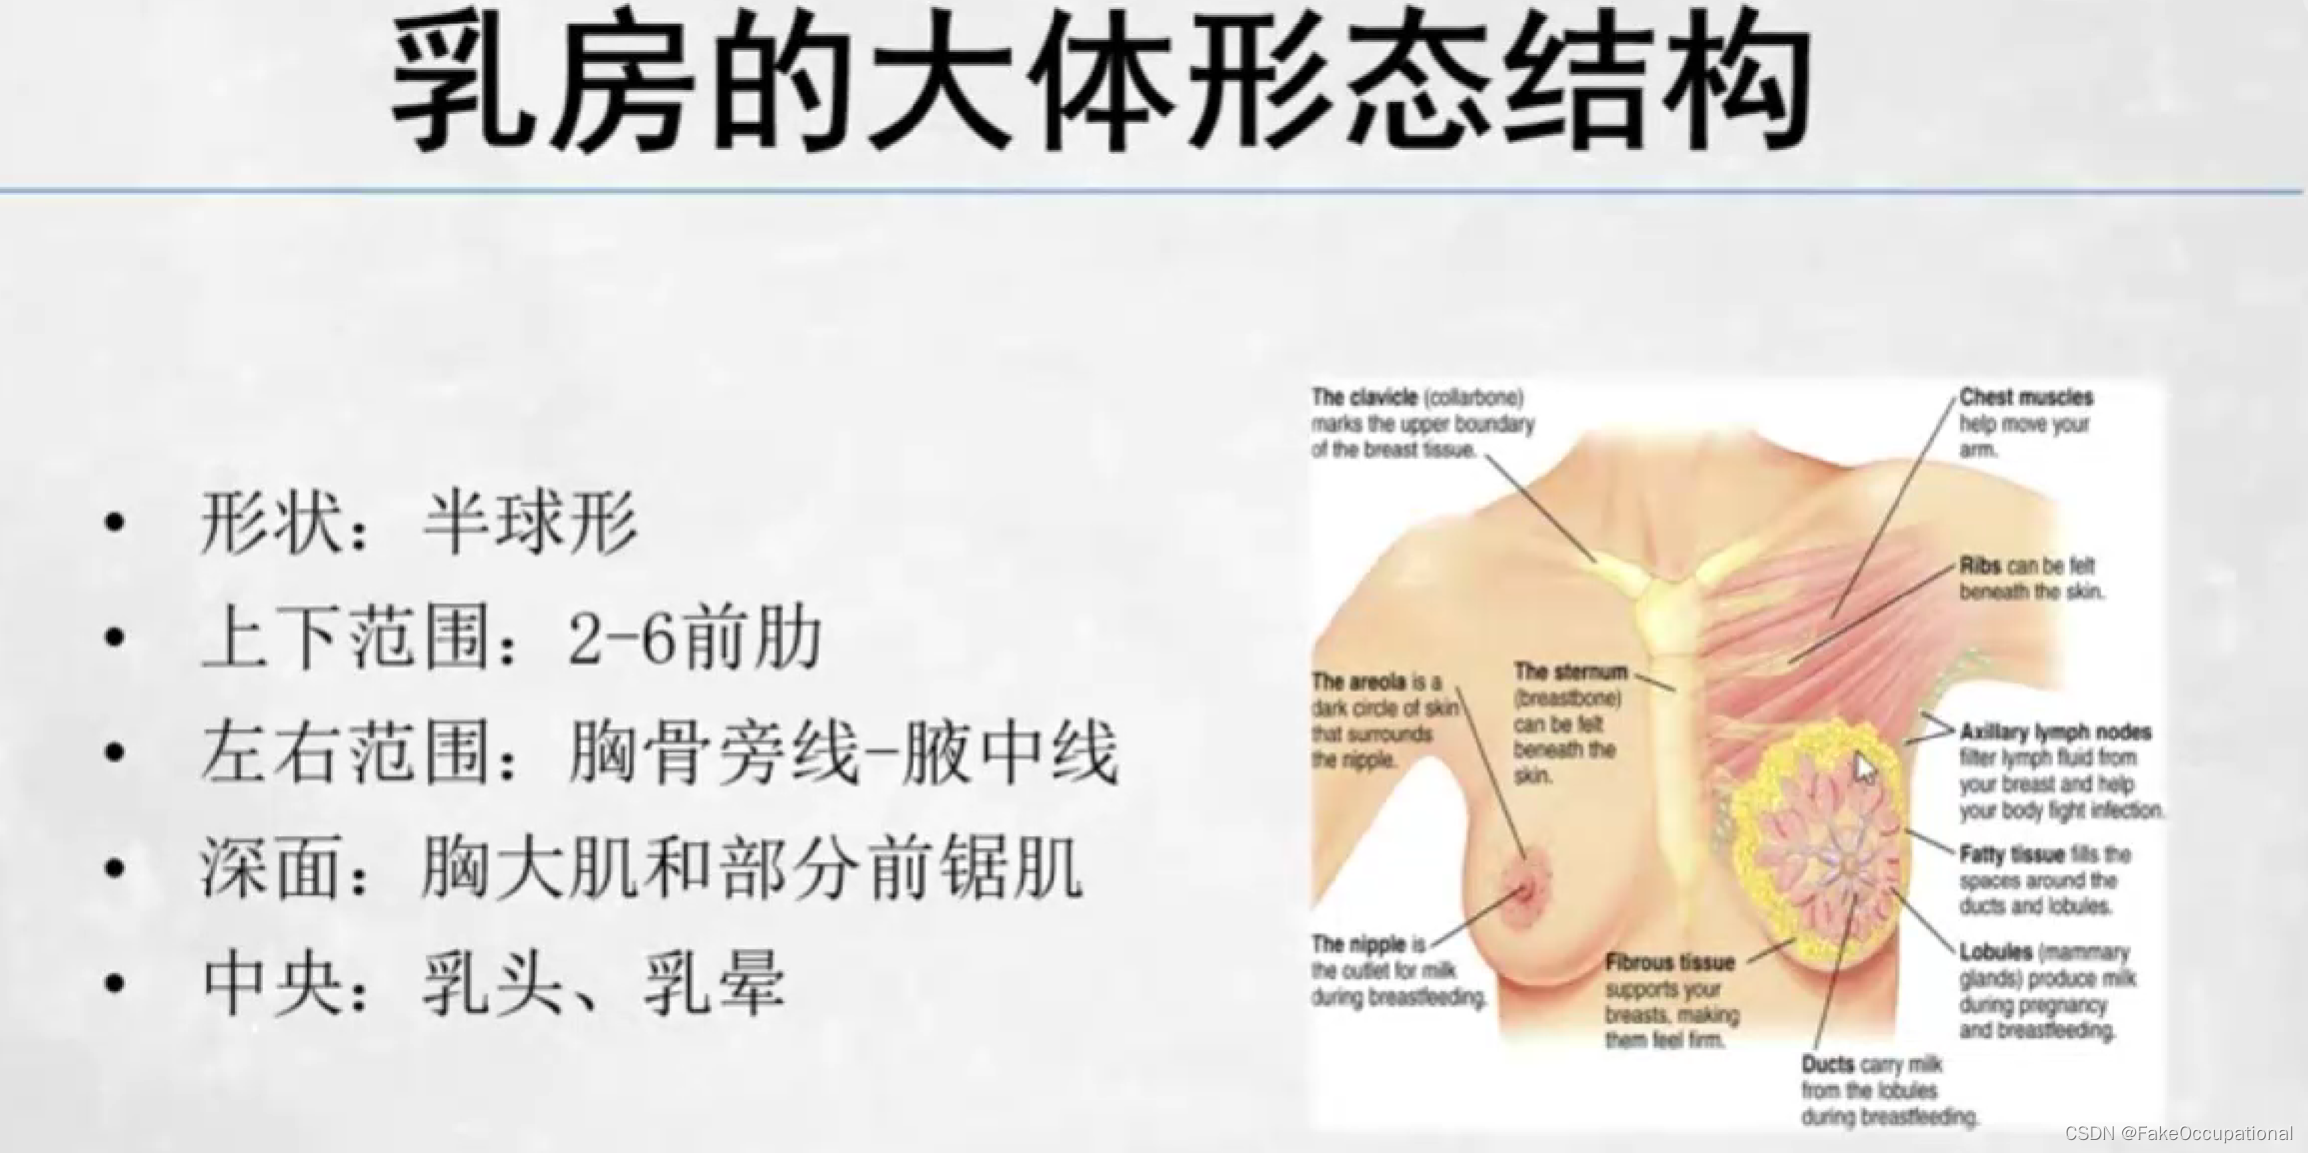

乳腺的生理解剖概要

乳腺的生理解剖概要